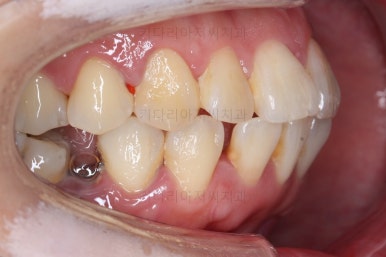

1. 초진

초진 시 입안의 모습입니다.

당장 눈에 띄는 부분은 아래 앞니 사이에 틈새가 있어 치석도 많이 쌓여있는 상황이고요.

윗니-아랫니를 각각 보면 치아가 썩고 부러져 뿌리만 남은 치아가 많이 보입니다.

남은 치아들도 곳곳에 충치가 보이고요.

또 전반적으로 앞니가 앞으로 밀려나와 뻐드러져 있는 모습도 관찰되네요.